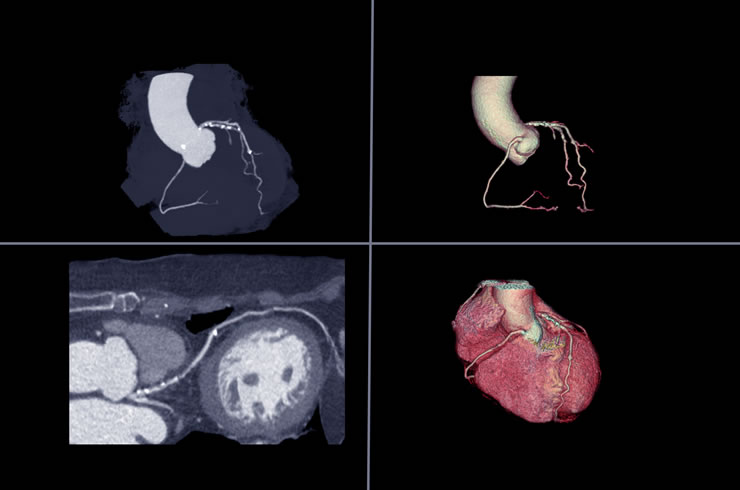

Αξονική στεφανιογραφία (CCTA)

Παρέχει λεπτομερείς εικόνες της καρδιάς και των αιμοφόρων αγγείων, βοηθώντας στην εκτίμηση της ανατομίας της στεφανιαίας αρτηρίας και της σοβαρότητας της νόσου.